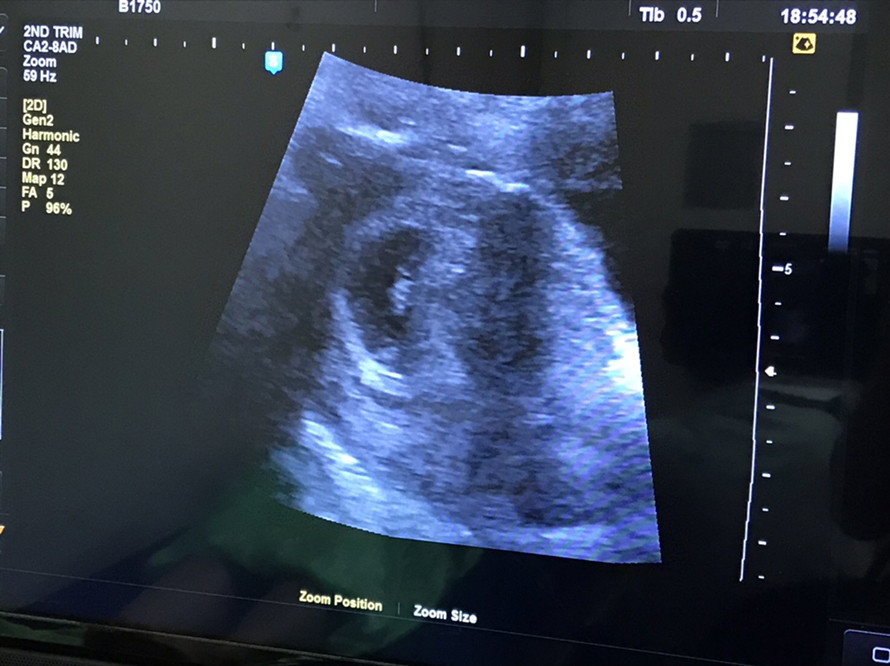

ตอน5วีคค่ะ ซาวผ่านช่องคลอดถึงเจอค่ะ แต่เจอแต่ถุงการตั้งครรภ์ ตอนนี้14วีคแล้วค่ะ

ตอนเรา5วีคหมอก็บอกแบบนี้ไม่ต้องกังวลน้องตัวเล็กอยู่ตอนนี้21วีคแล้วค่ะ

6w ค่ะ น้องอาจจะยังเล็กอยู่ค่ะเลยทำให้ไม่เห็นน้อง คุณแม่ใจเย็นๆนะคะ